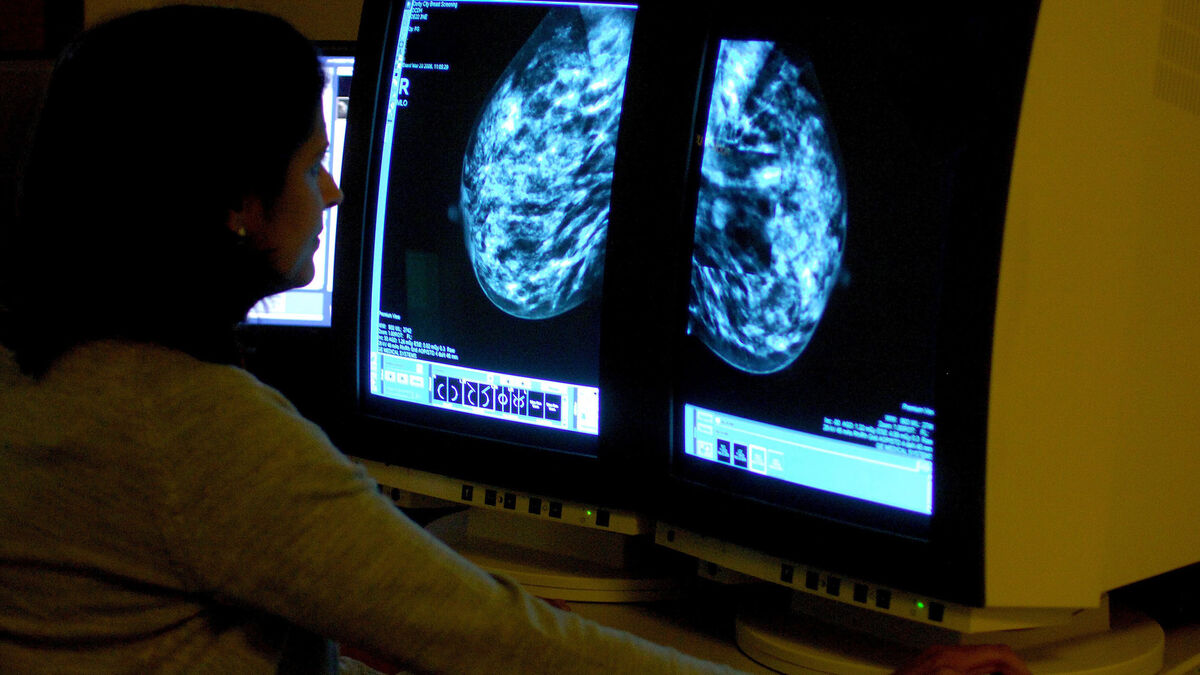

Irish Cancer Society director of advocacy Steve Dempsey pointed to reports last year that BreastCheck had missed its target of 195,000 screenings in 2024 by just under 30%. Stock picture